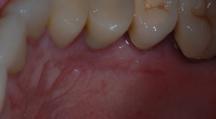

Figure 7.1 Récessions gingivales multiples.

7.1 QU’EST-CE QU’UNE RÉCESSION GINGIVALE ?

Une récession gingivale, encore appelée dénudation radiculaire ou déhiscence est une dénudation partielle de la face extérieure des racines, nommée face vestibulaire (face visible) due à la migration de la gencive. Elle n’est pas d’origine bactérienne mais plutôt traumatique. De fait, elle n’est pas un signe de parodontite.

Une gencive anatomiquement fine, soit naturellement, soit du fait d’une position excentrée de la dent sur l’arcade, associée à un brossage traumatique ou encore à des mouvements orthodontiques qui déplacent la dent vers

l’extérieur pour permettre son alignement sont autant de causes d’apparition d’une récession gingivale.

En aucun cas, la récession gingivale ne peut être responsable à elle seule de la perte de la dent.

En revanche, elle peut rapidement rendre la dent hypersensible aux variations thermiques ou à certains aliments. Elle complique le brossage car la limite dent-gencive ne se trouve

plus au même niveau que la dent adjacente. Une inflammation gingivale peut s’installer, rendant la zone sensible. Enfin elle peut être jugée inesthétique en donnant l’impression visuelle d’une dent très longue.